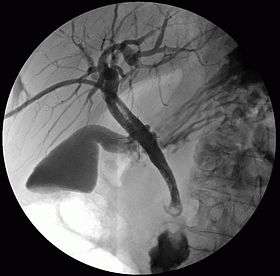

Percutaneous transhepatic cholangiography (PTHC or PTC) or percutaneous hepatic cholangiogram is a radiologic technique used to visualize the anatomy of the biliary tract. A contrast medium is injected into a bile duct in the liver, after which X-rays are taken. It allows access to the biliary tree in cases where endoscopic retrograde cholangiopancreatography (ERCP) has been unsuccessful. Initially reported in 1937, the procedure became popular in 1952.[1][2]

It is predominantly now performed as a therapeutic technique. There are less invasive means of imaging the biliary tree including transabdominal ultrasound, magnetic resonance cholangiopancreatography, computed tomography and endoscopic ultrasound. If the biliary system is obstructed, PTC may be used to perform biliary drainage until a more permanent solution for the obstruction is performed (e.g. surgery). Additionally, self expanding metal stents can be placed across malignant biliary strictures to allow palliative drainage. Percutaneous placement of metal stents can be utilised when therapeutic ERCP has been unsuccessful, anatomy is altered precluding endoscopic access to the duodenum, or where there has been separation of the segmental biliary drainage of the liver, allowing more selective placement of metal stents. It is generally accepted that percutanous biliary procedures have higher complication rates than therapeutic ERCP. Complications encountered include infection, bleeding and bile leaks.